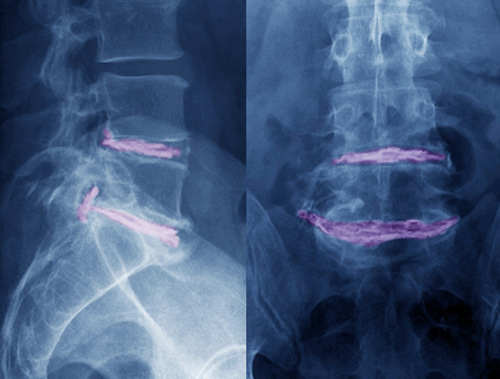

Pasienter med vedvarende eller residiverende isjias blir gjerne henvist til gjentatte MR-undersøkelser av ryggen. En nederlandsk forskergruppe har undersøkt sammenhengen mellom funn ved MR-undersøkelse og isjiasplager hos 267 pasienter ett år etter at de fikk isjias med MR-påvist skiveprolaps. 224 pasienter (84 %) var da helt eller nesten helt kvitt sine plager. Skiveprolaps og nerverotaffeksjon ble påvist på MR like hyppig hos pasientene som var blitt friske (henholdsvis 35 % og 24 %) som hos dem som hadde restplager eller nye isjiasplager (henholdsvis 33 % og 26 %). Prolapsens størrelse og type (skivebukning eller ekstrudert prolaps) var heller ikke assosiert med pasientens plager.

– Denne studien viser bildediagnostikkens begrensninger for å forklare hvorfor pasienter får ryggsmerter, sier Kjell Arne Kvistad, seksjonsoverlege ved Klinikk for bildediagnostikk, St. Olavs hospital. – I flere studier er det dokumentert at degenerative forandringer påvist på MR, inkludert skiveprolaps i lumbalryggen, har liten eller ingen korrelasjon til forekomst av ryggsmerter. Denne studien understreker at når pasienter med residiv av isjiassmerter etter prolapskirurgi skal vurderes for reoperasjon, er det sykehistorien og de kliniske funnene som er viktigst, ikke funn ved bildeundersøkelser, sier Kvistad.